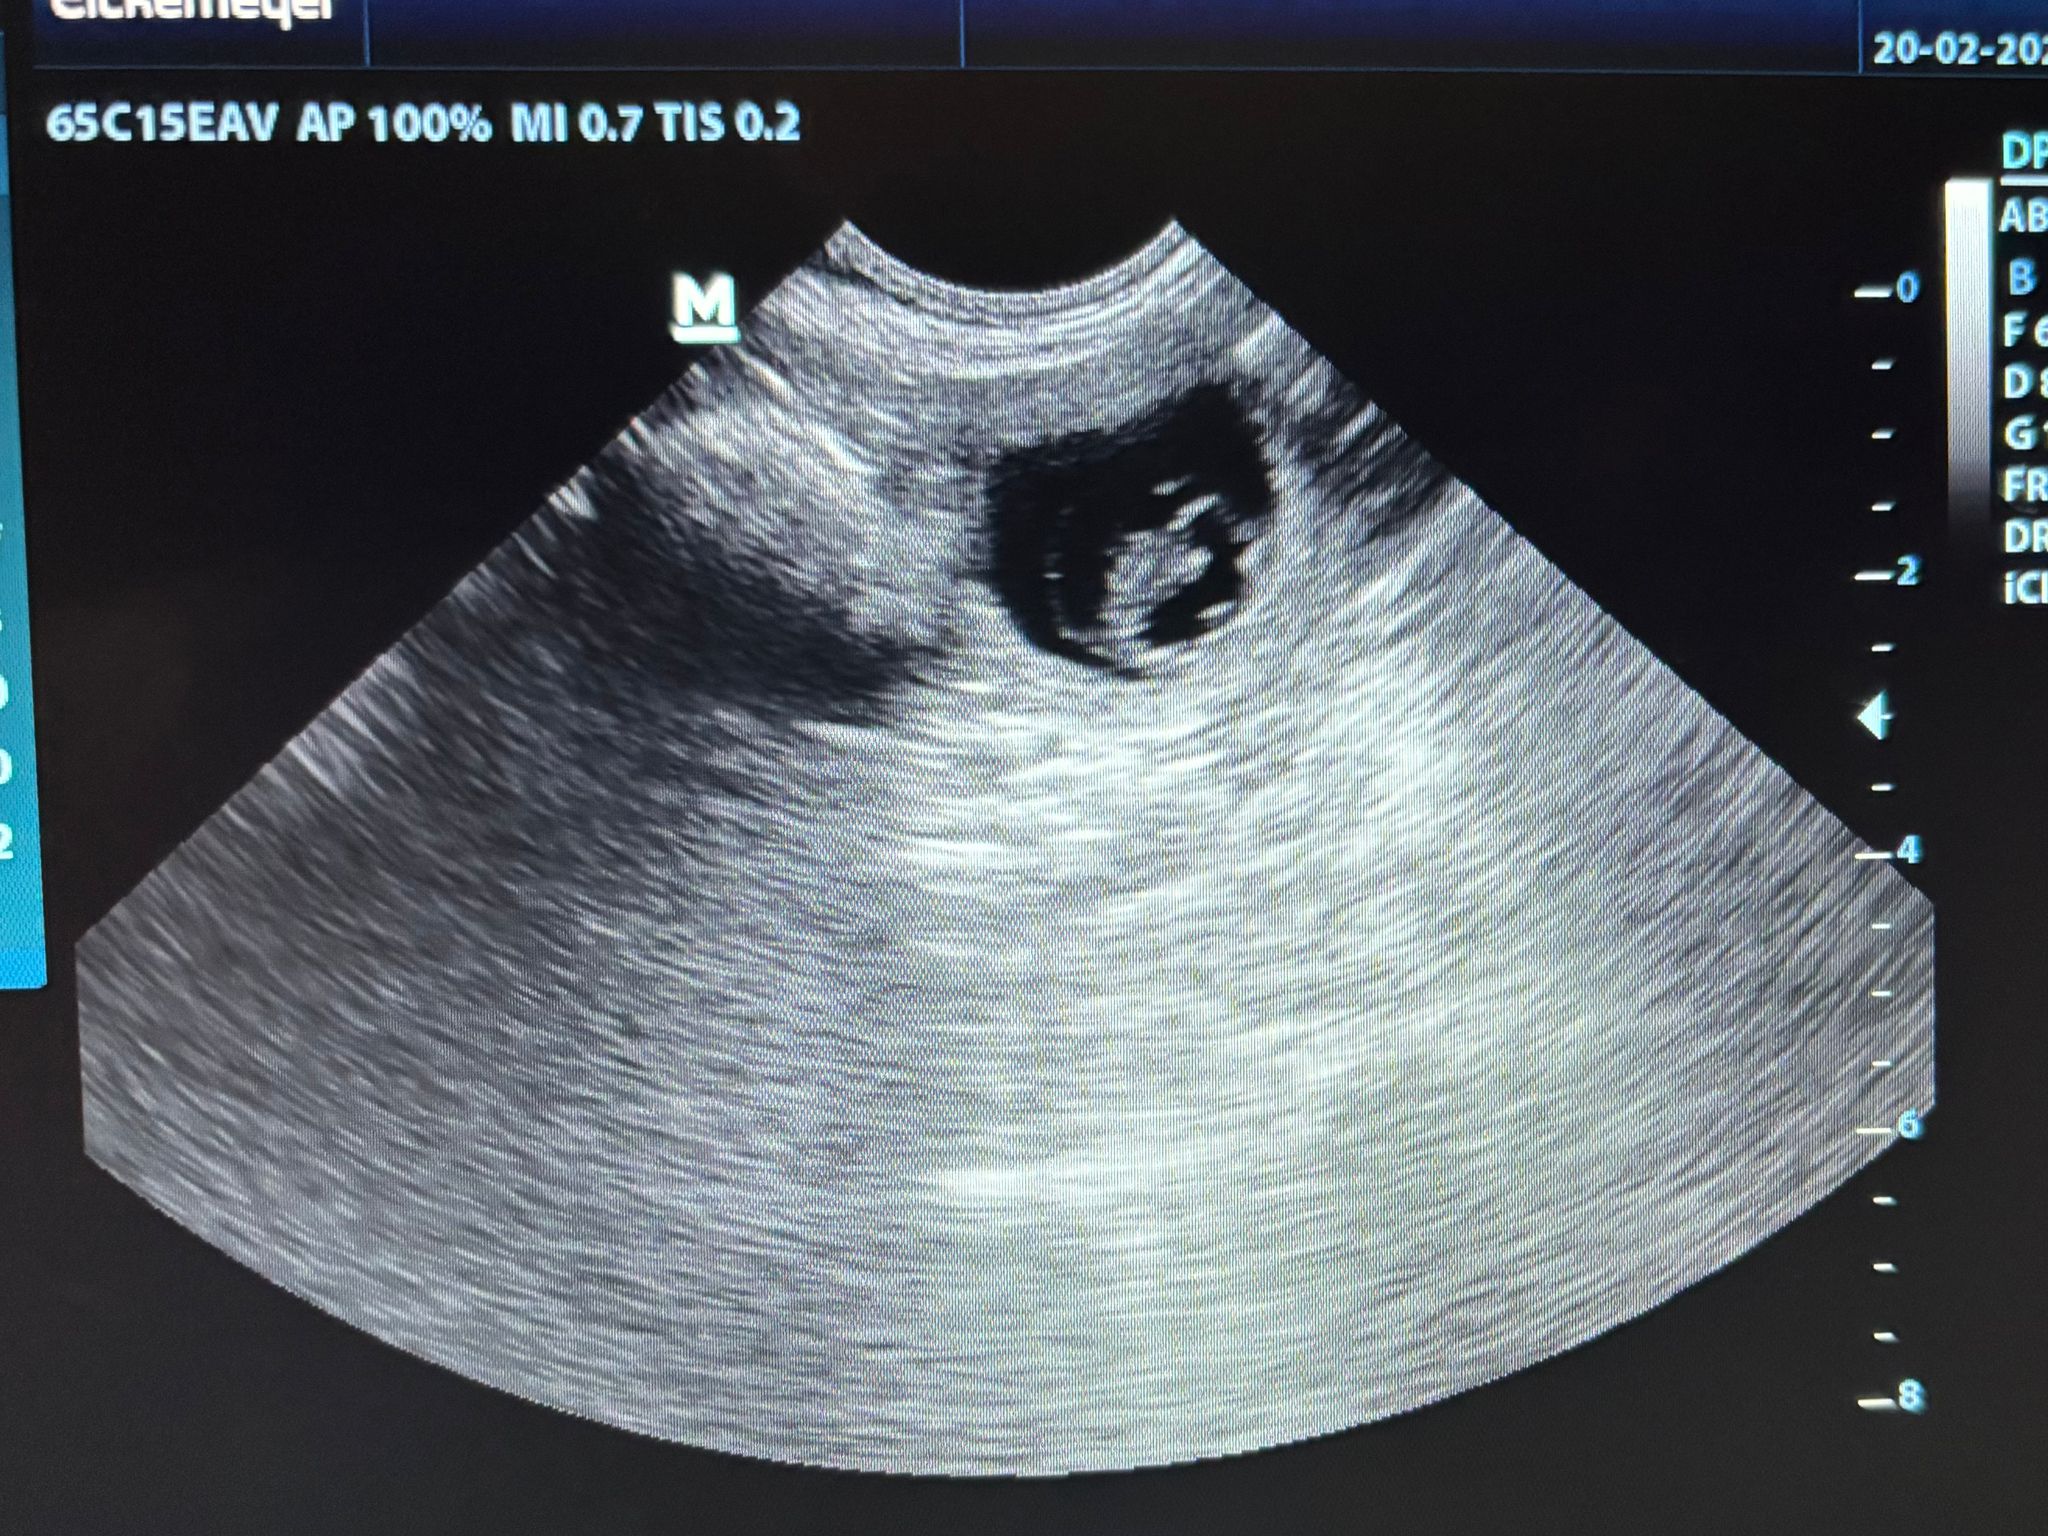

Beim Ultraschall bei unserer Tierärztin hat sich gestern Abend (19.2.2026) gezeigt, dass unsere Maite vom Nikolausberg nun trächtig ist und aus der Verpaarung mit unserem Duke Ellington kleine English Cocker Spaniel Welpen bekommen wird. Wir sind schon so gespannt auf den A-Wurf.

Am 26. März 2026 wäre der berechnete Wurftag aufgrund des 1. Deckakts. Der Ultraschall zeigt aber wohl, dass sie noch kleiner sind und ein späterer Deckakt wahrscheinlich dazu führte.

Deshalb ist es wahrscheinlicher, dass der Wurftag auch ein paar Tage später sein könnte. Eine fast genaue Anzahl der Welpen können wir erst beim Röntgen sehen, das ca. 1 Woche vor dem Wurftag erfolgt. Dann lassen wir uns überraschen, wieviel Rüden und Hündinnen es sind, und welche Farben sie haben, wenn es soweit ist...